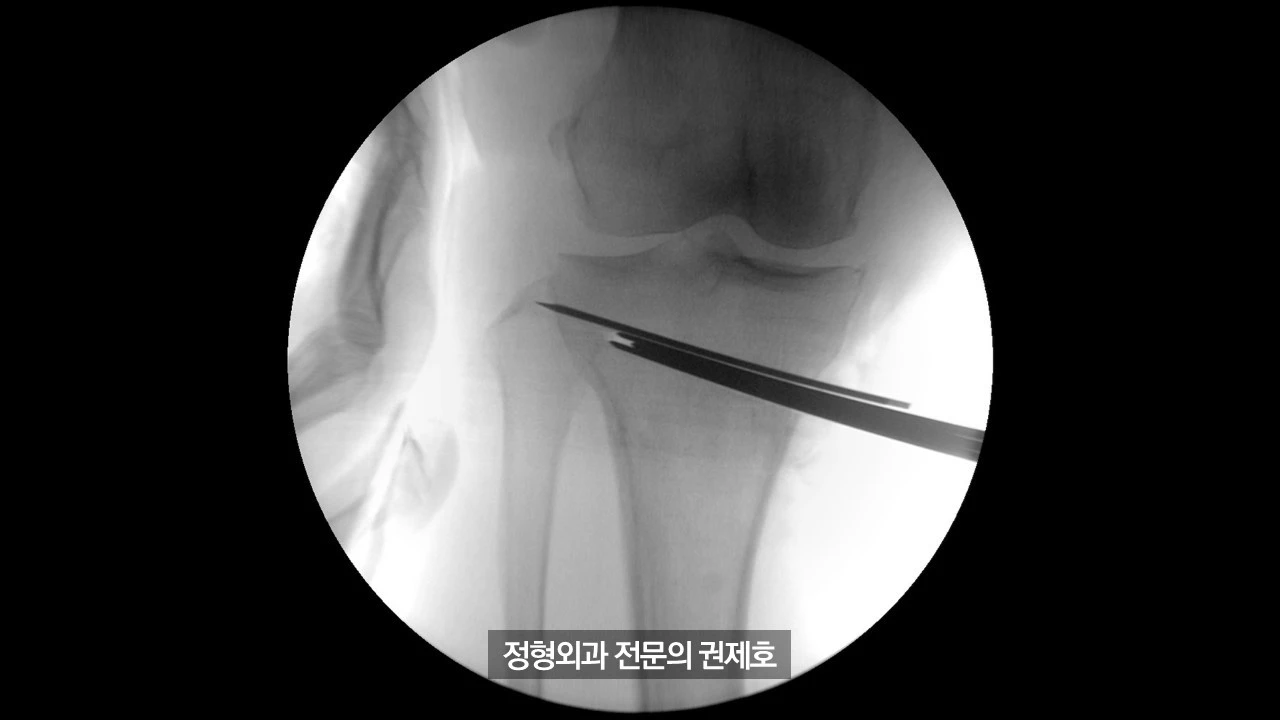

간이 엑스레이 기기를 통해 촬영한 사진이며 (좌측) 가이드 핀을 이용해서 절골할 길을 만드게 되고, (우측) 절골도를 이용하여 천천히 절골을 시행하게 됩니다.

절골도를 이용한 절골이 완료가 되면 이제 절골도 3개를 넣어서 천천히 늘리게 됩니다.